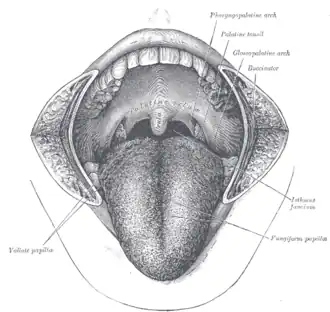

The mouth cavity: The cheeks have been slit transversely and the tongue pulled forward.

The mouth cavity: The cheeks have been slit transversely and the tongue pulled forward. -